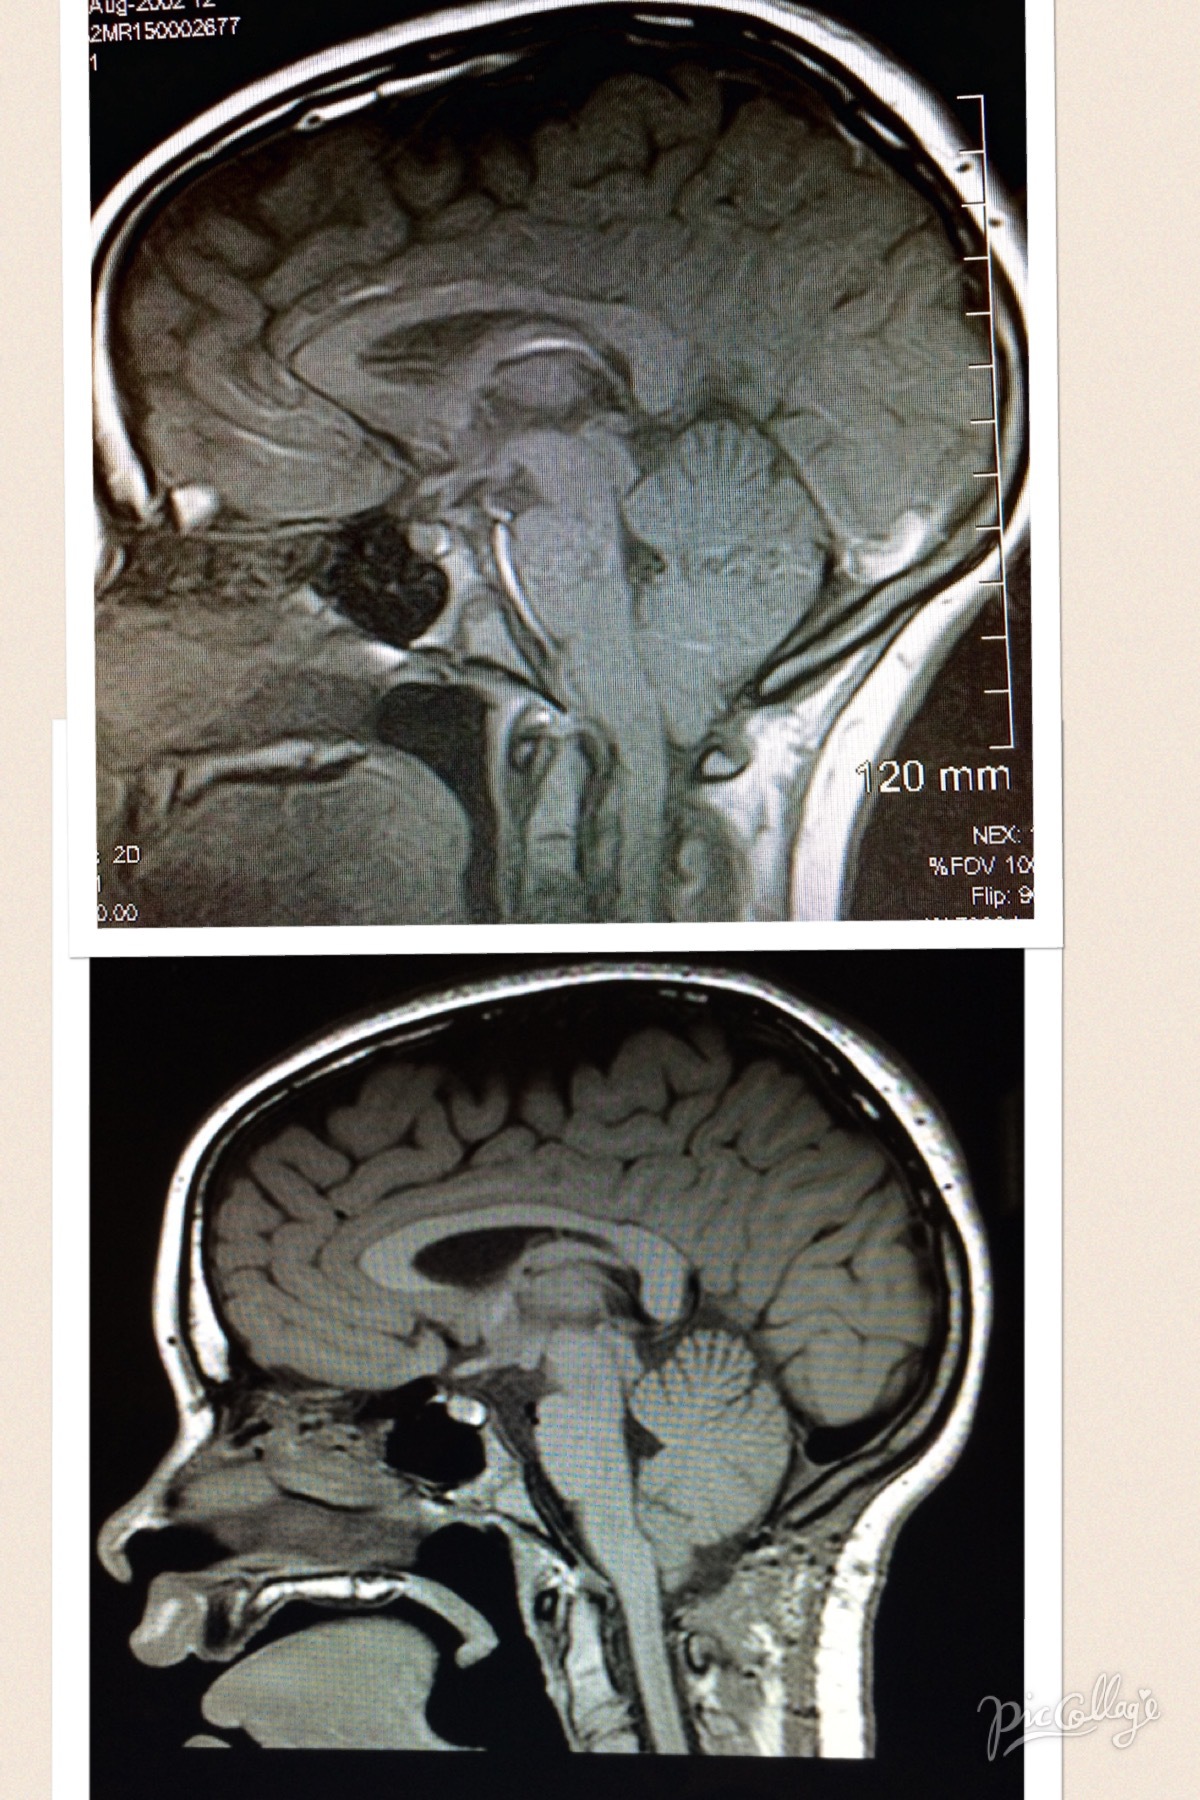

Hello, I wanted to tell my daughter's story. My daughter is 13 yrs old. She was born healthy. I tried to nurse her but quickly became frustrated. Unlike my older daughter, she did not nurse well. I switched to the bottle and she continued to have feeding issues. We finally put her on the hypoallergenic formula and fed her in an upright position as much as possible. She spit up all the time! Then as a toddler she had bowel issues and Miralax was our best friend for years. Then came the sensory issues, ADHD, Pica, Asperger's, Alice in Wonderland Syndrome (yes there is such a thing), and general anxiety diagnoses. She spent a year and a half in occupational therapy for sensory issues and motor skills. She caught up on most of the motor skills and learned some coping skills for sensory stuff. We always carried ear muffs like they wear on the gun range because she could not handle noise. She complained since preschool that her hands hurt/cramped after writing for a few minutes. She tired easily and complained that her legs hurt. I was so tired of hearing "my head and stomach hurt". We spent years going to doctors including neurologists, had EEG's and other tests done. Everything would come back normal. Then in February of 2015 the headaches became daily. She could not function at school after a few hours. The principal would call and tell me to come get her. Her teacher told me that she could tell when the headaches would start getting bad. She said my daughter would become pale, her demeanor would change, and she would start rubbing her head. My daughter would finish her class work before asking to go to the nurse. We went back to the neurologist and he said it was migraines and gave us some medication. We tried the medication for a couple of weeks with no relief. Called him and all he would say is keep using the medicine and he would see her in four months. We started searching for a new neurologist and found one but we have to drive almost an hour to see her. Our first visit and she says "has no one done a scan of this poor child's head?" She was hired!! In early June, almost five months later, the MRI results came back. Chiari 1 Malformation with a 9mm descent of the tonsils. Then came the fun part, finding a neurosurgeon. The first one was a definite flop who said surgery would not fix or help her! Then July 1st we met with another surgeon in Dallas, TX who said he thought surgery was the only option. So on August 20th just a few days after her 13th birthday, she under went the 5 hour decompression surgery at Children's Medical Center in Dallas. That was the longest five hours of our lives. The surgeon did a posterior fossa decompression and opened the dura. She spent 24 hrs in ICU and was released after two days in a regular room. Recovery has been slow and hard at first. She missed the first semester of school but had a teacher who came to our house twice a week to help her. She has not had "one of those headaches" since surgery. Her hands and legs do not hurt anymore. She no longer wear ear muffs or complains about noise. She is a new kid, doing things that she never would have done before. She was withdrawn and shy before, but now she wants to be around people. For the first time she wants to go to school! Her principal is amazed at the difference and so are we. There are good stories and successful surgeries. She will always live with Chiari, but it doesn't dictate her life anymore! She has days that she just doesn't feel 100% but that is better than before. It has been exactly six months and we feel like we have definitely done the right thing! Sorry this is such a long post. The top is before surgery and the bottom is 4 months after surgery.